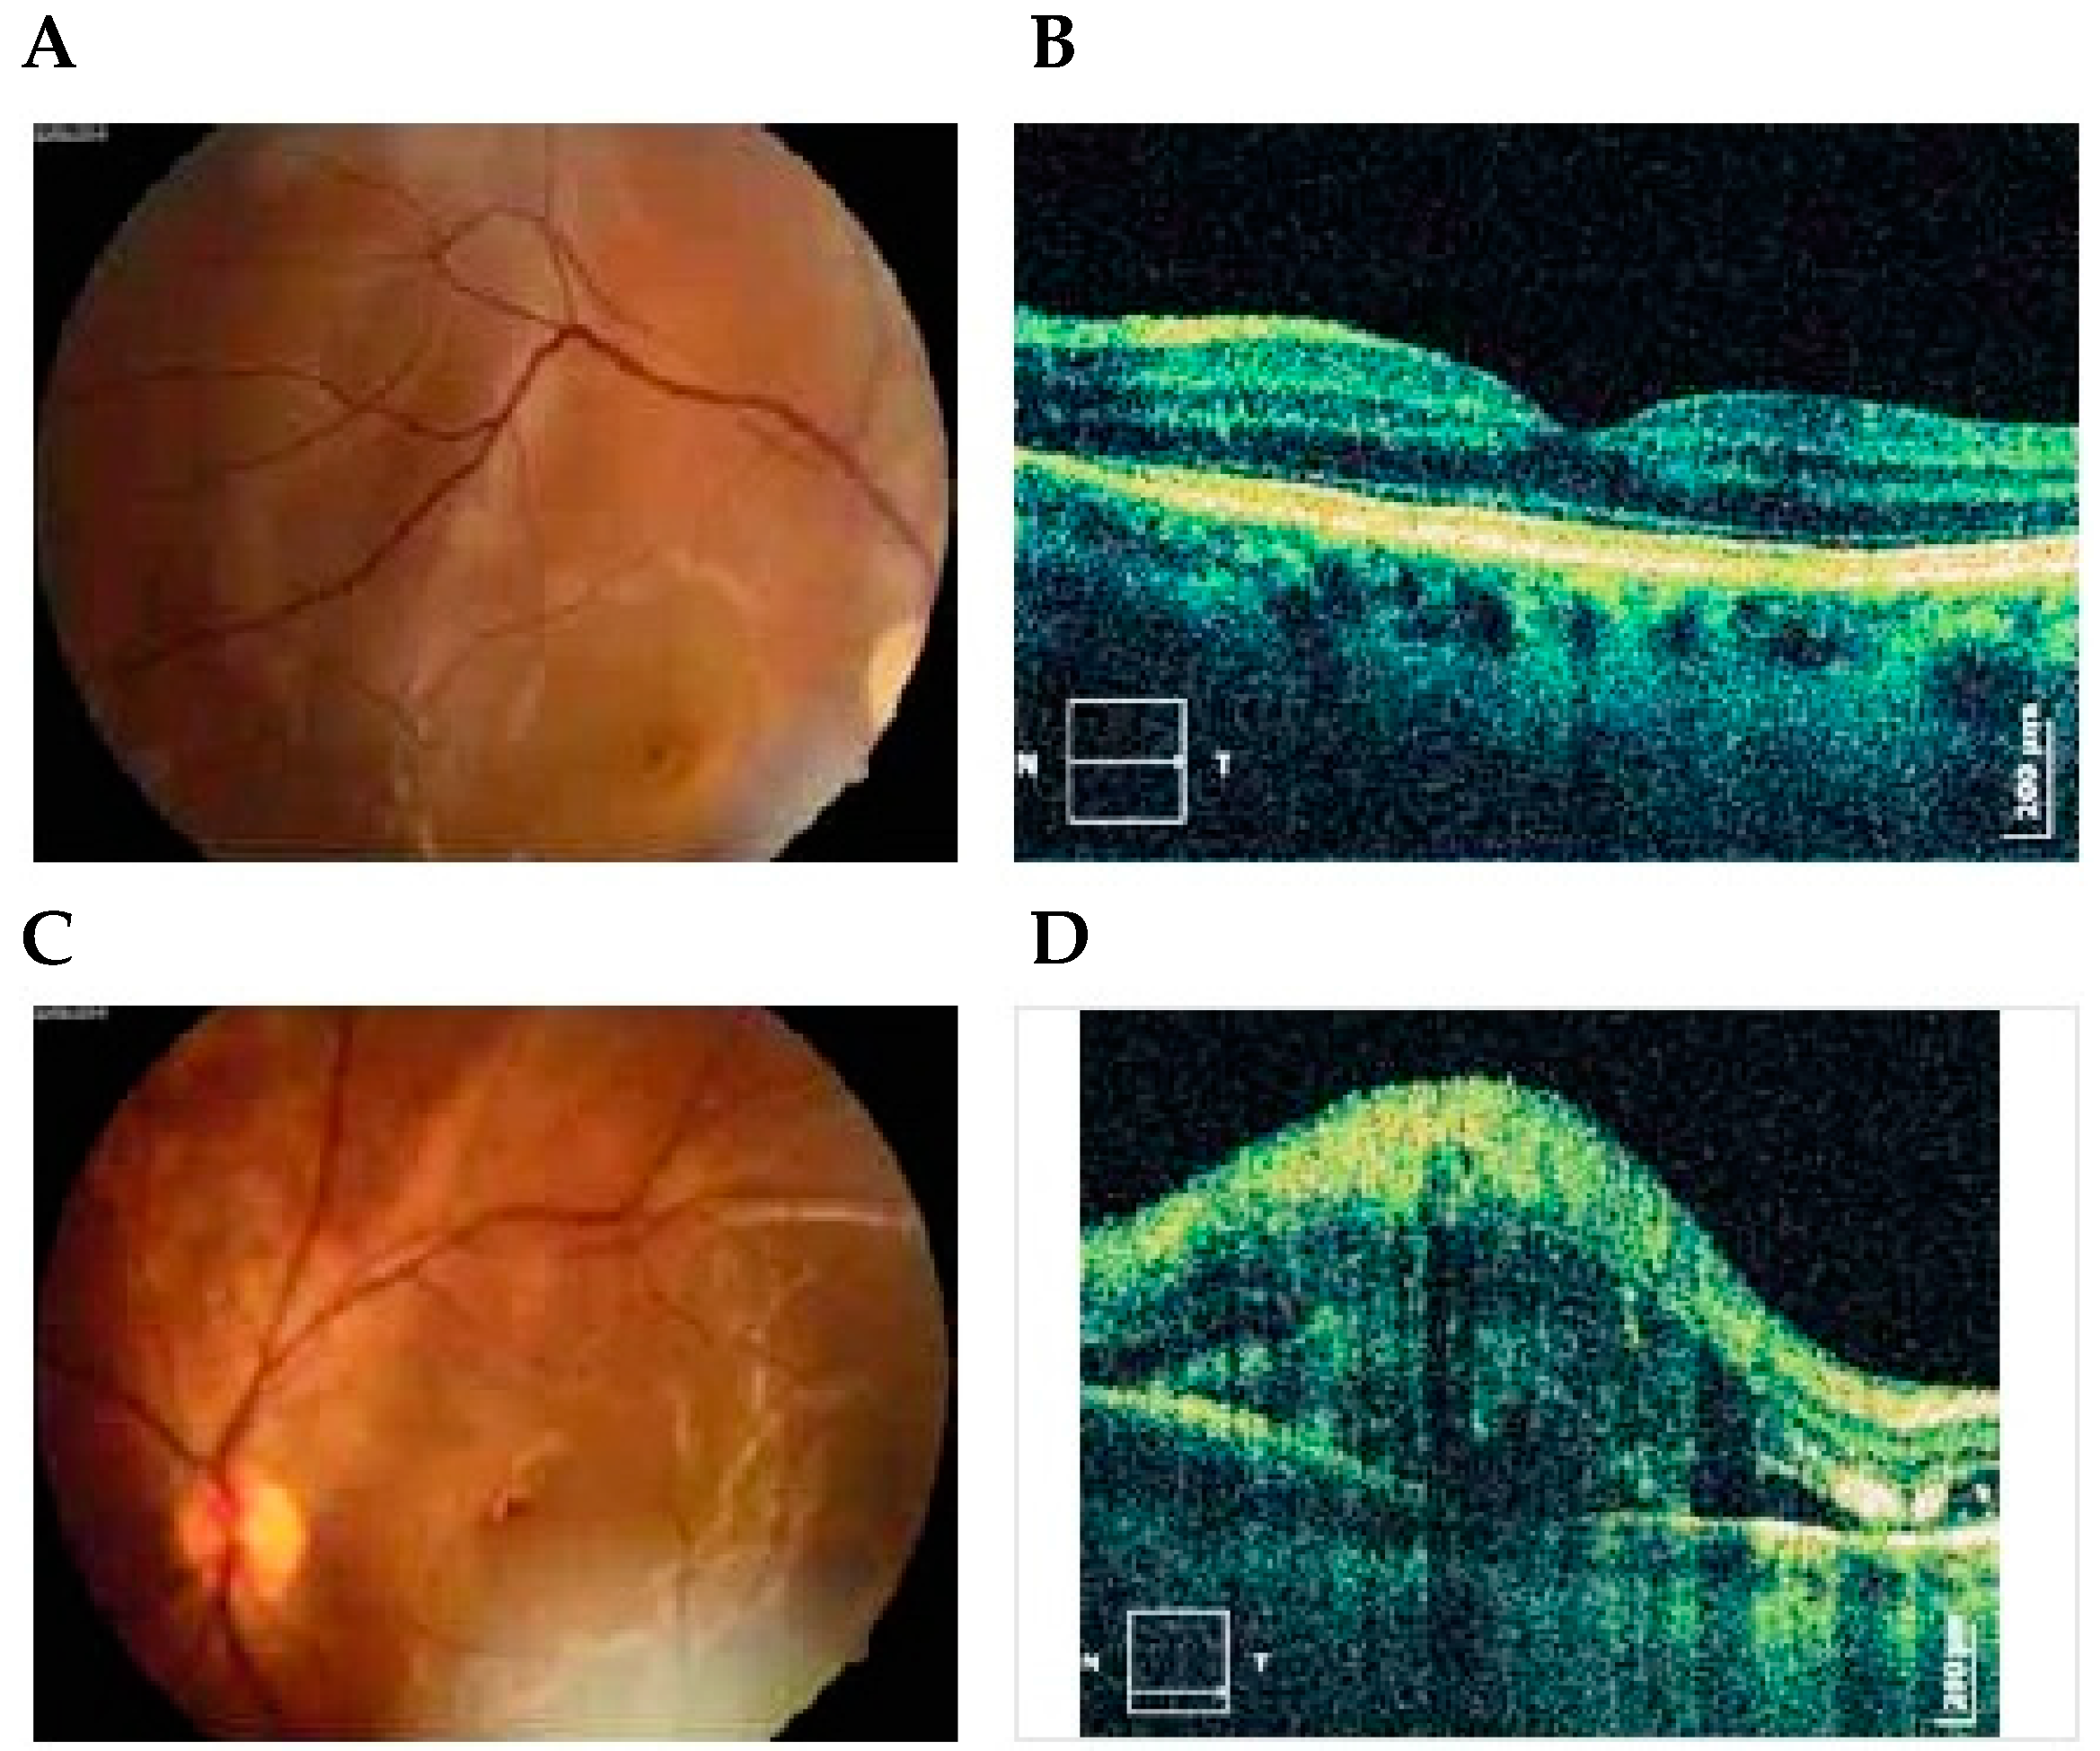

6. OCT

Multinodal Imaging

- Theodossiadis, P.G.; Kollia, A.K.; Gogas, P.; Panagiotidis, D.; Moschos, M.; Theodossiadis, G.P. Retinal disorders in preeclampsia studied with optical coherence tomography. Am. J. Ophthalmol. 2002, 133, 707–709. [Google Scholar] [CrossRef]

- Wang, Z.; Zou, Y.; Li, W.; Wang, X.; Zhang, M.; Wang, W. Application of optical coherence tomography and contrast sensitivity test for observing fundus changes of patients with pregnancy-induced hypertension syndrome. Medicine 2015, 94, e1641. [Google Scholar] [CrossRef] [PubMed]